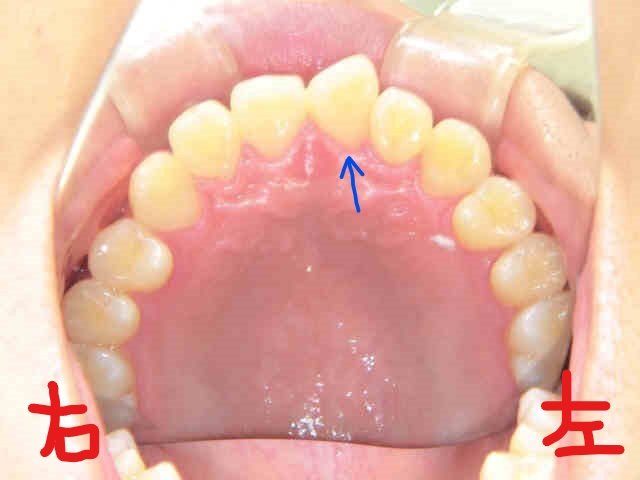

左上の写真は、上顎前歯にブラケット(ボタン)を装着した直後の状態、右上がブラケット装着前に上顎を下から見上げた写真です。主訴である左上の前歯がかなり捻転している様子がご確認いただけると思います。